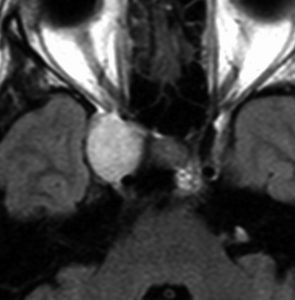

左聴力低下で発症した小脳の海綿状血管腫で,小脳橋角槽に突出するように増大しています。

左上が発症時,次が1ヶ月後,3ヶ月後,4ヶ月後と急速に大きくなったので摘出しました。

静脈奇形を伴っていませんでした。